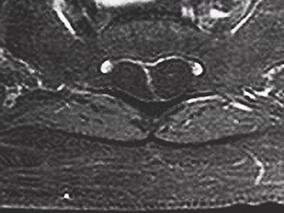

1小时条评论【病例资料】 患者,男性,34岁。因双下肢麻木无力、跛行半年,二便困难3个月于2013年2月16日入院。 现病史:患者于半年前无明显诱因出现双下肢无力,以右下肢为著,伴双膝以下发凉、麻木感,不伴有下肢肿胀、关节畸形,上述症状逐渐加重,出现右下肢行走困难,伴...